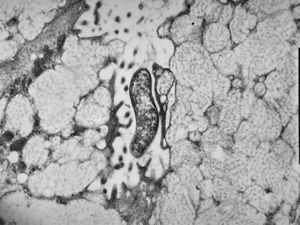

normal mucosa - jejunum - microvilli(anchored core rootlets)

normal mucosa - jejunum - microvilli